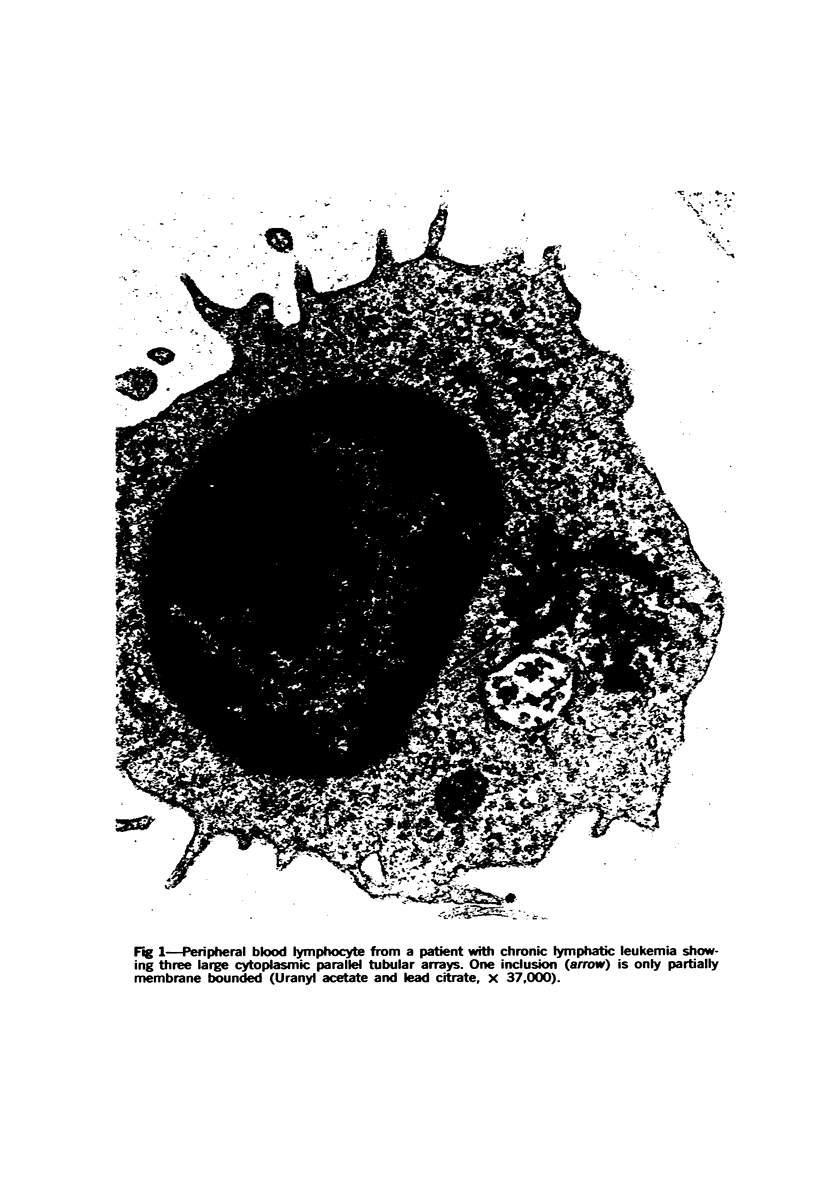

Parallel tubular inclusions were found in peripheral blood lymphocytes from 18 patients with various hematologic disorders, primarily lymphoproliferative processes, and 1 apparently healthy individual. The inclusions varied in size from 1000 to 6000 A and were usually membrane bounded. The microtubule-like structures comprising the inclusions ranged in size from 150 to 300 A and were packed in wall-to-wall contact with each other. Dense amorphous material and small dark crystalloids were frequently noted in the inclusions. There appeared to be a spatial and structural relationship of the inclusions with the centriole. The highest percent of lymphocytes with inclusionss (greater than 90%) were found in a patient with a lympho-proliferative disorder in whom 95% of the peripheral blood lymphocytes typed as T cells by spontaneous rosette formation with sheep red blood cells. (Am J Pathol 78:59-70, 1975)